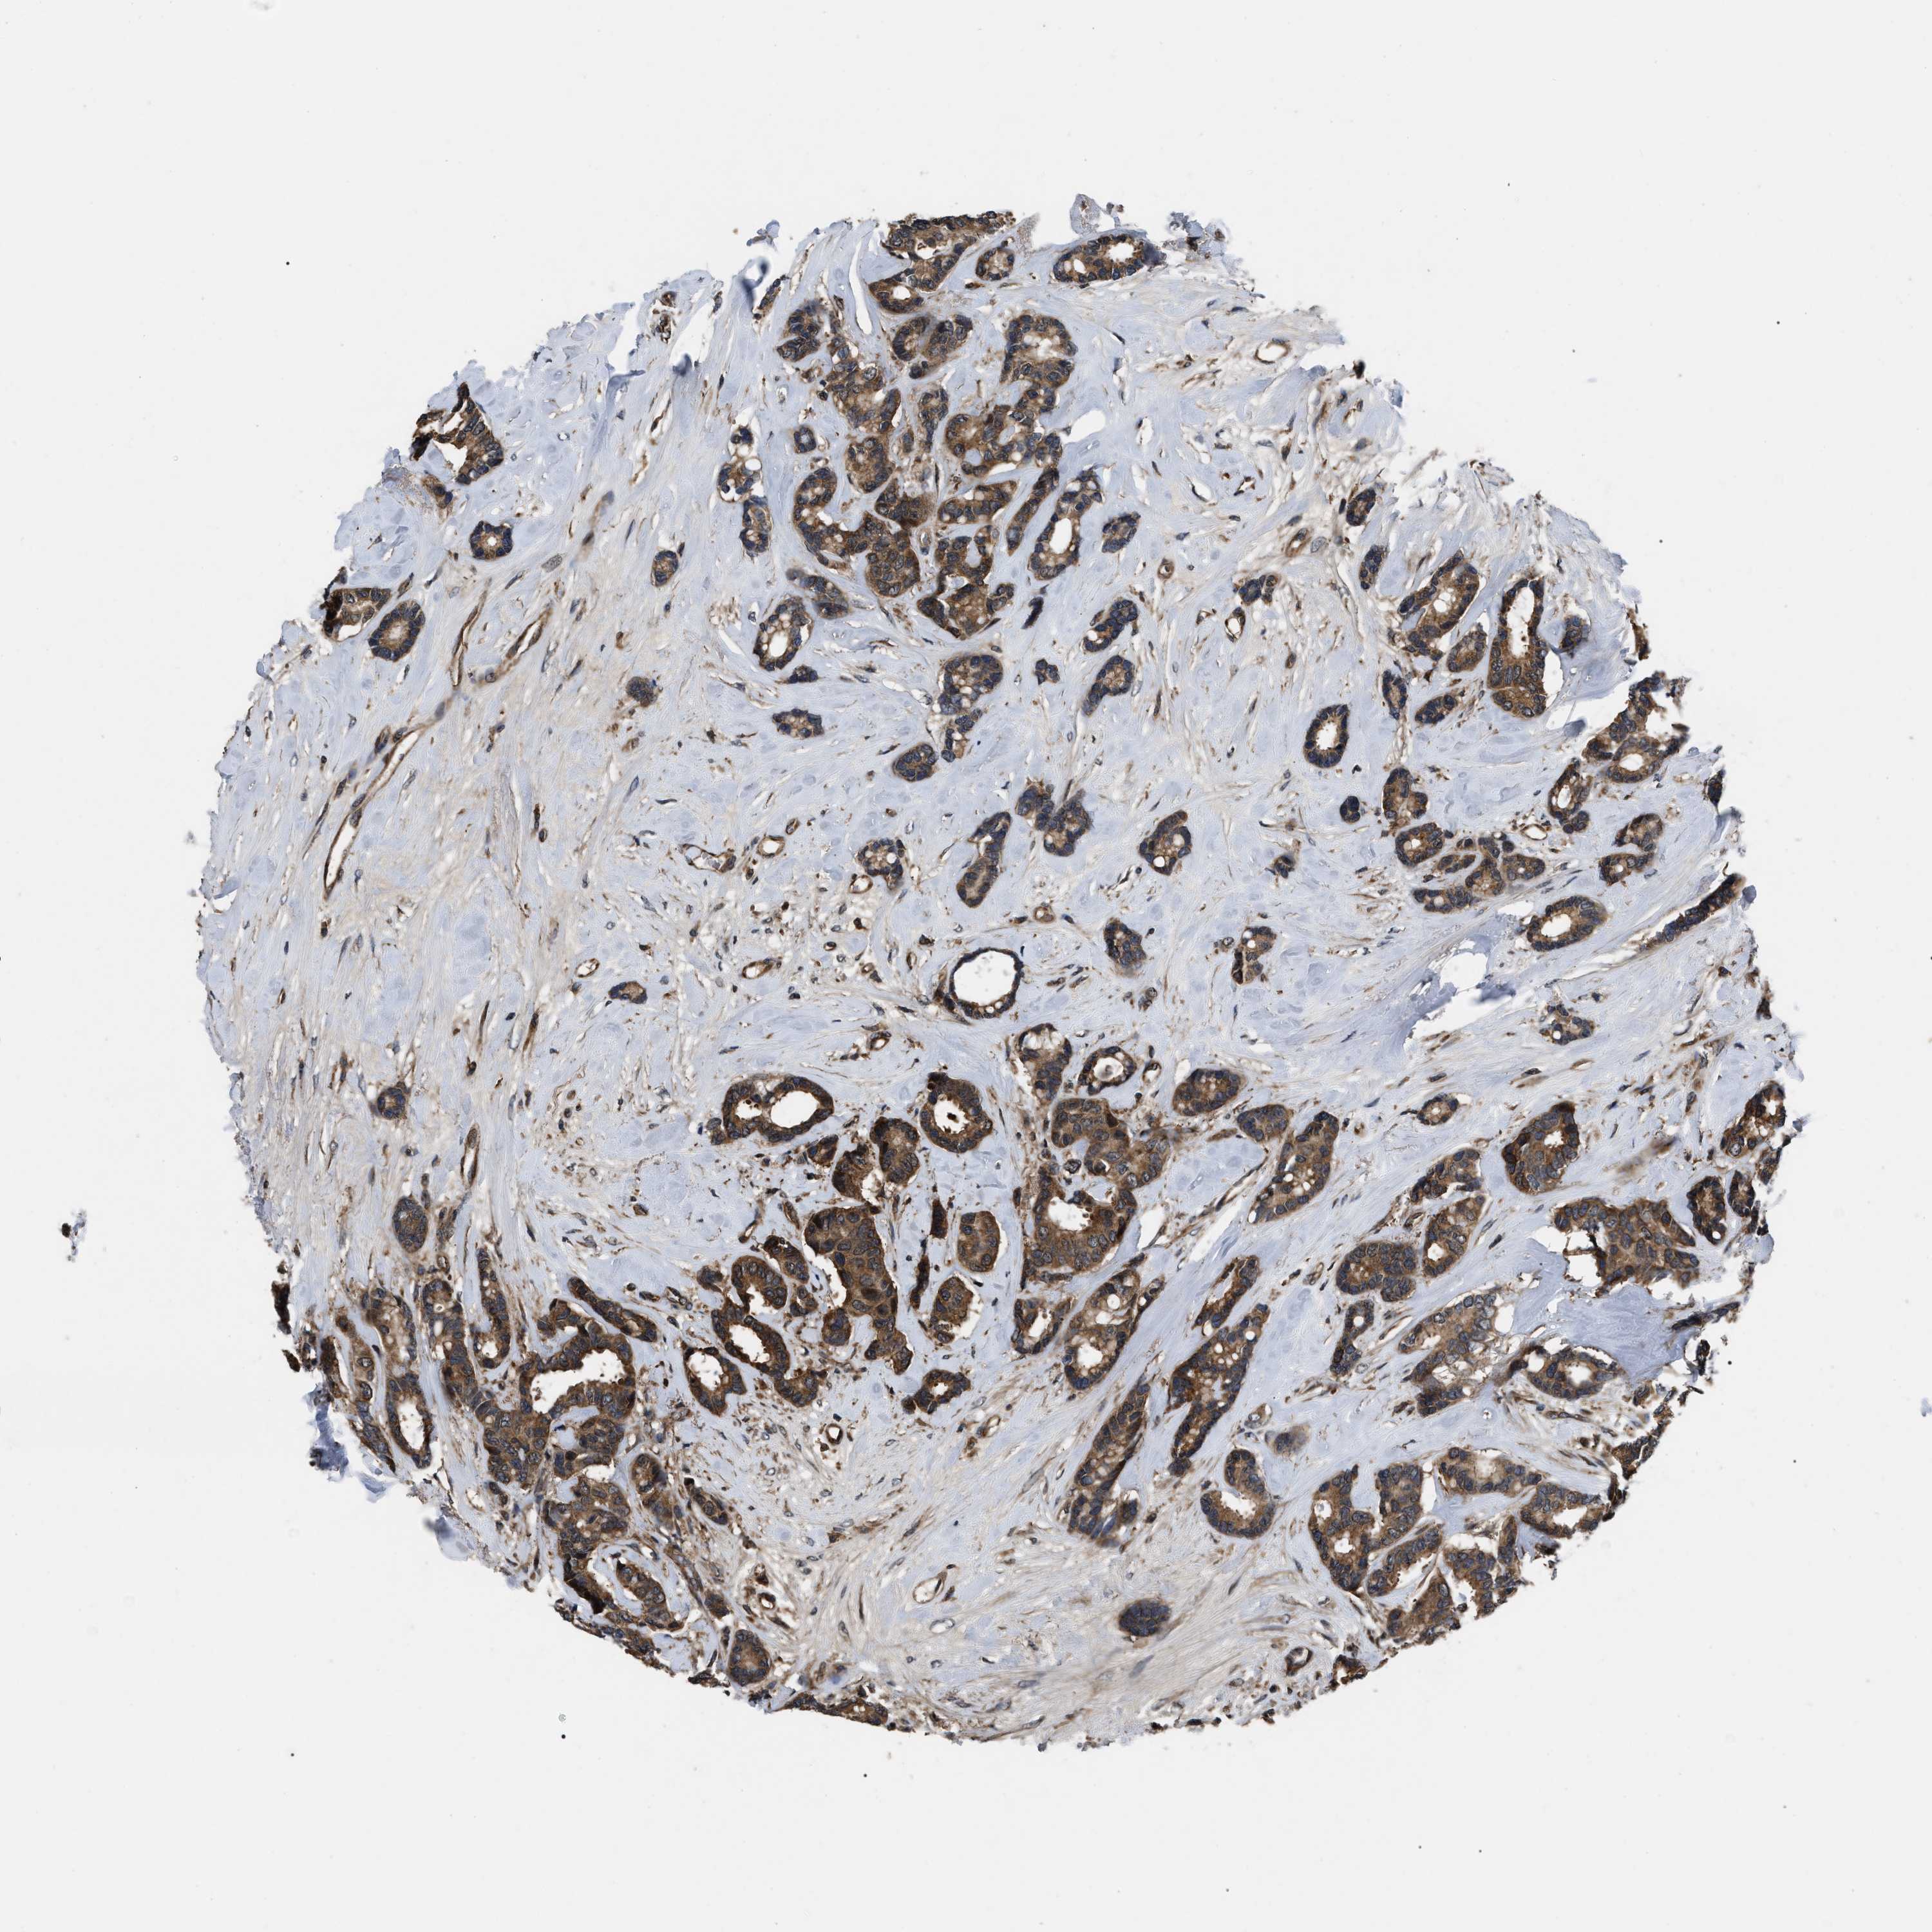

CANCER BREAST CANCER Show tissue menu

BRCA TCGA BRCA VALIDATION PROTEIN EXPRESSION